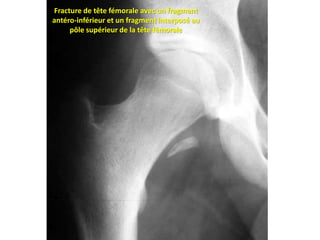

Une place particulière est à donner aux fractures de

l’acétabulum que l’on rencontre dans 20 % des luxations

postérieures (Fig. 4), et aux fractures de la tête fémorale qui

représentent 13 % des cas.

Fracture de tête fémorale avec un fragment

antéro-inférieur et un fragment interposé au

pôle supérieur de la tête fémorale

Fracture de têtefémorale avec un fragment antéro-inférieur et un fragment interposé au pôle supérieur de la tête fémorale